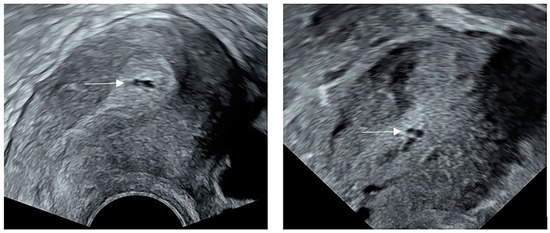

2.3. Ultrasonography Examination